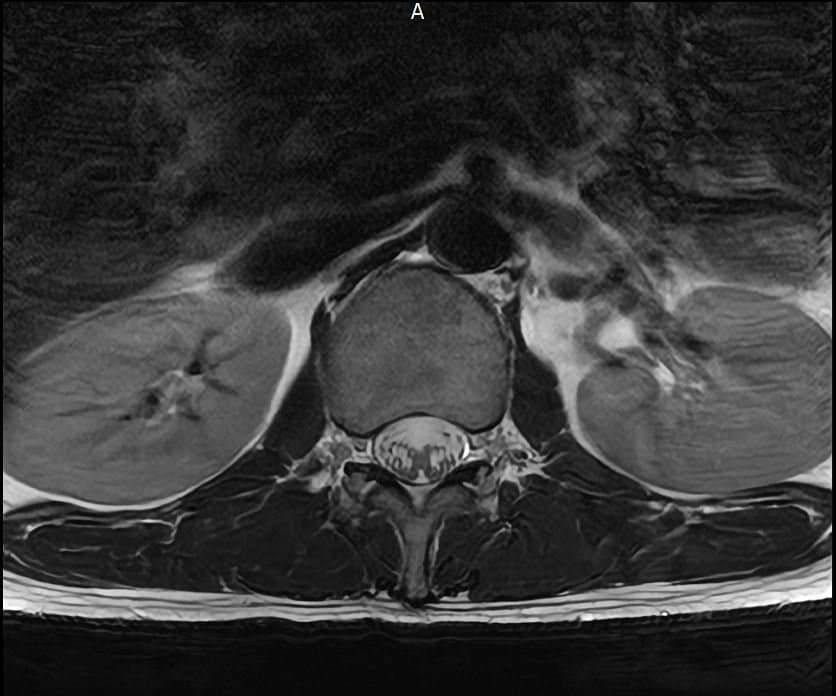

양쪽 엉덩이 염좌 6주째인데 mri 촬영한것좀 봐주세요

엉덩이 양쪽 염좌가 6주됨

방사통 없음 저림 없음 재채기 , 계단타기 전부 정상 , 숙일때 통증 없음

엉덩이 위쪽 바깥쪽 부분이 아픔 압통점 있음

177 / 66kg 약간의 퇴행성이 보인다는데 엉덩이 염좌와는 연관 없을꺼라고 하는데

영상과 증상을 종합해보면 전체적으로 척추배열은 양호하나, 요추4~5번과 요추5번~천추1번 사이의 디스크 수핵이 약간 검게 변한 퇴행성 변화가 관찰됩니다. 다만 신경을 심하게 압박하는 추간판탈출증 소견은 뚜렷하지 않습니다.현재 방사통이나 저림이 없고 특정부위에만 압통이 있다면 의료진의 소견대로 허리디스크보다는 근육 몇 인대문제일 가능성이 높습니다.말씀하신 부위는 염좌로 인해 예민해진 근막이나 인대가 완전히회복되지 않아 컨디션에 따라 통증이 반복될수 있습니다. 6주째 통증이 반복된다면 단순 휴식보다는 물리치료나 도수치료를 통해 굳어있는 근막을 풀어주는 것이 회복에 도움이 됩니다. 빠른쾌유를 빕니다!

MRI 영상상 관절 주변 조직의 부종이나 구체적인 염증 부위를 세밀하게 확인하는 과정이 꼭 필요해 보입니다.